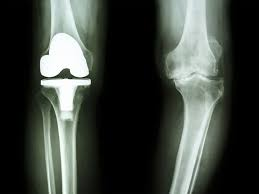

この筋肉内への脂肪浸潤は、全身にわたる筋肉の質を損なう全身性の問題であり、下肢の関節変形(変形性股関節症、変形性膝関節症)を発生させて、関節手術が必要な最悪な状況へと陥れます。

研究者らは、これらの筋肉内への脂肪沈着が筋肉再生の物理的な障壁として機能し、関節の安定に不可欠な大腿四頭筋とハムストリングを弱めることを発見しました。

MRI画像の所見

・筋線維の萎縮(衰弱)→筋力の脆弱化とサルコペニア

・筋線維間への脂肪沈着:筋肉の霜降り化

肥満による関節への負荷が増大し、“股関節・膝関節・足関節の軟骨の損傷→関節変形”を発症し、歩行が困難になったり、人工関節置換術などの人工関節挿入手術が必要になってしまいます。